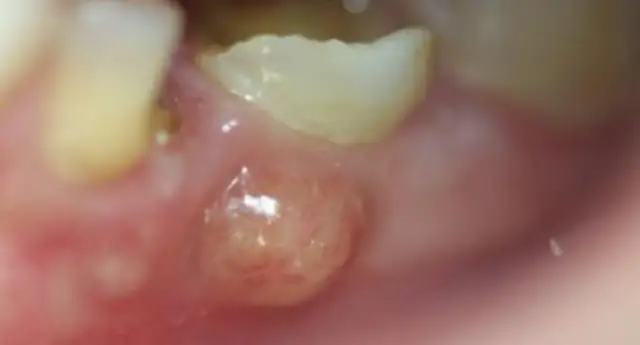

Jednakże, jeśli zapalenie dziąseł jest długotrwałe i nieleczone, może przejść w kolejną, znacznie groźniejszą fazę paradontozę, czyli periodontitis. Paradontoza jest chorobą nieodwracalną. Atakuje ona nie tylko dziąsła, ale także głębsze tkanki przyzębia, w tym kość szczęki i żuchwy, która stanowi podporę dla zębów. Nieleczona paradontoza prowadzi do rozchwiania zębów, a w konsekwencji do ich utraty.

Kluczowa różnica między tymi dwoma stanami polega więc na odwracalności procesu i zakresie uszkodzeń. Zapalenie dziąseł to stan początkowy, dotyczący głównie tkanki dziąsłowej. Paradontoza to zaawansowana choroba, która niszczy struktury kostne. Niestety, zapalenie dziąseł jest często pierwszym, ignorowanym krokiem do rozwoju paradontozy. Ryzyko progresji choroby jest największe właśnie wtedy, gdy bagatelizujemy jej wczesne objawy. Warto też wiedzieć, że pojawienie się ropnej wydzieliny z kieszonek dziąsłowych jest sygnałem, że choroba jest już w zaawansowanym stadium.